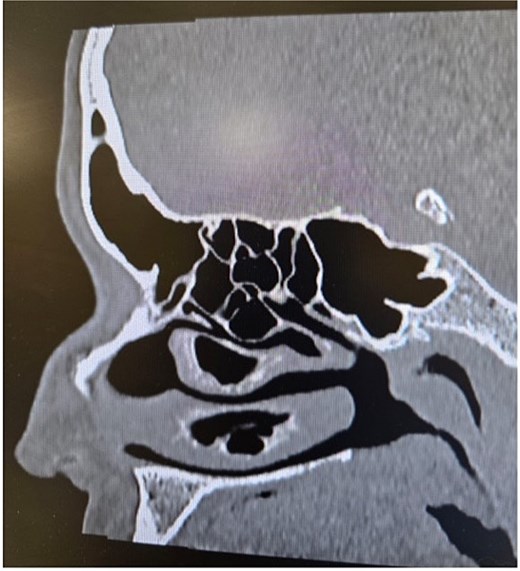

Clinical examination, including anterior rhinoscopy and nasal endoscopy, revealed a midline nasal septum and bilateral hypertrophy of the inferior and middle turbinates, with otherwise normal nasal mucosa. A CT scan of the paranasal sinuses in the coronal plane demonstrated bilateral pneumatization of the middle turbinates consistent with CB. Additionally, the right inferior turbinate was pneumatized, with communication to the ipsilateral maxillary sinus (Figs 1 and 2).

Paranasal sinus CT scan in the coronal plane demonstrating bilateral inferior concha bullosa with communication to the maxillary sinuses.